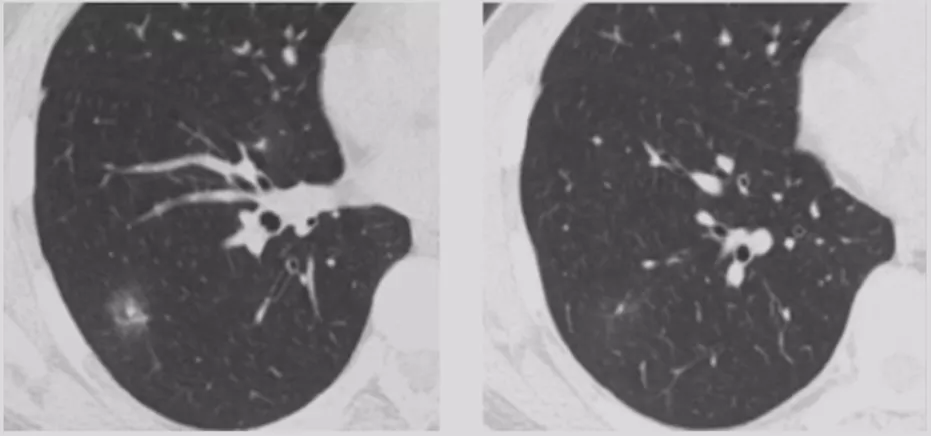

在临床上经常手术切除后发现是AAH,关于AAH的病人是否需要手术还存在很大的争议,有的认为不需要手术,观察就可以。那么我们在术前怎么评判是否为AAH?其实具有一定特征。一般来说,多位于肺外周,多<5mm,圆形或类圆形,边界清楚,多发更常见,绝大部分是均匀的纯磨玻璃影,里边没有实性成分。组织学检查AAH呈轻度到中度非典型立方柱状上皮细胞沿肺泡和呼吸性细支气管上皮增殖,无浸润,这样在临床上诊断AAH应该没有问题。但是,如下图所示,这个病人是多灶性病变,现在多灶性结节有所增多,会给临床的处理上带来一定压力。